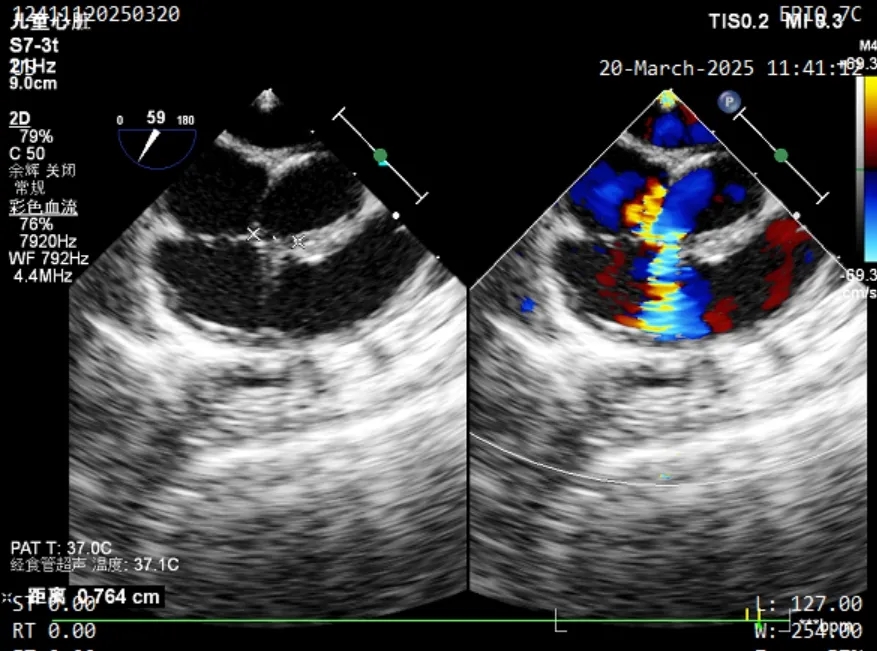

缺损情况:术中食道超声复测为膜部瘤型室缺,瘤体基底宽约7.6mm,两处破口分别宽约1.3mm及2.3mm。

术中超声复测

膨出瘤基底部宽约7.6mm

两处破口分别宽约2.3mm及1.3mm

术中食道超声复测发现本例为膨出瘤型室缺并伴有多破口,瘤体基底宽约7.6mm, 两处破口分别宽约1.3mm和2.3mm。由于金属封堵器盘面展开易受膨出瘤限制,可能无法完全覆盖所有破口,存在残余分流风险。而全降解封堵器凭借其良好的柔韧性,植入后既能够自适应膨出瘤复杂的结构形态和组织运动,又可确保完全封堵。术者经综合考虑后,最终选择使用ABFDQ-I 5规格的全降解封堵器进行封堵。术后超声显示,封堵器形态良好,封堵完全,无残余分流。术后1个月随访,封堵器位置形态良好,患者恢复情况良好。